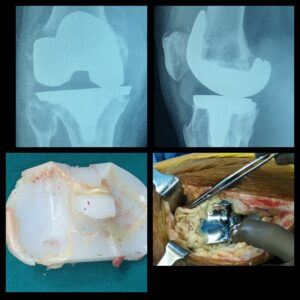

History: 75 yrs old male was unable to walk or perform basic leg movement due to an adverse knee inflammation from a failed primary knee replacement implant

Case: Dr. Amyn Rajani had conducted a revision of primary knee replacement surgery for this man as the implantations from the previous knee replacement surgery done elsewhere loosened and caused several damages to his knee joint. Referring surgery to a well-experienced and highly trained surgeon becomes a necessity in such cases. It is important that we avoid considering surgery from young, untrained surgeons and opt for those who have high experience and expertise in the given field of surgery.